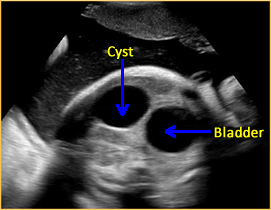

Urachal Cyst: Images

Above. Urachal cyst. Note the anechoic connection between the fetal bladder and the umbilicus.

Above. Urachal cyst. Color Doppler demonstrates blood flow through the umbilical vessels but no blood flow to the cyst itself, which excludes the possibility of umbilical vein varix.

Above. Note the fetal bladder and the anechoic extension of a cyst-like structure superiorly.

Above. Urachal cyst. 23 weeks. Same patient as above showing an anechoic structure extending to the umbilicus. Color Doppler showed no flow within the cyst.